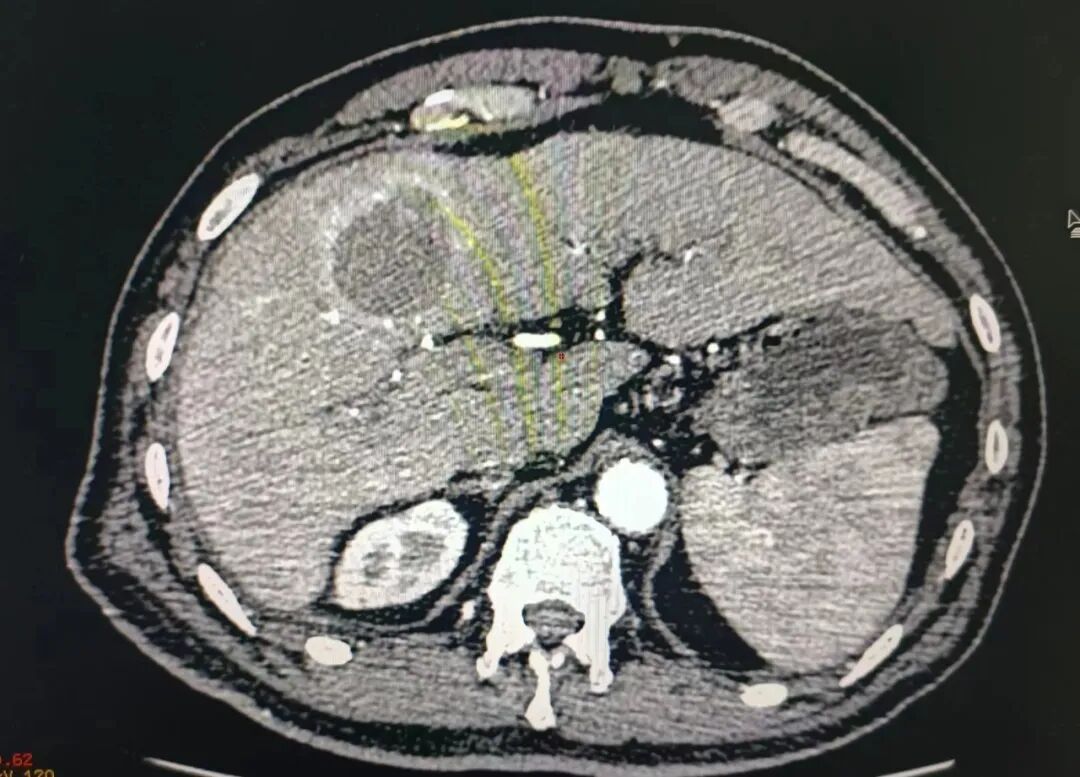

患者王先生,因酒精肝、肝硬化来我院住院治疗,住院期间发现肝S4低回声占位,考虑肝癌可能。

经多科讨论及研究后,经家属同意后,行超声引导下肝右叶肿瘤穿刺活检术及微波消融术,手术在南方医科大学南方医院吴凤林教授为技术指导下,功能科主任黄亮、医生严家伟、护士陈桃配合操作下。整个手术操作时间30分钟,过程顺利,术中及术后无明显疼痛。

(术前)

(术中)

肝癌的微创消融治疗是在超声或者CT的引导下,将针形器具通过皮肤插入到肿瘤的局部,通过射频或微波等能量形式使针形器具前端发热,导致局部的温度增加。当温度增加到一定程度,并持续一定的时间之后,就会造成针尖的组织坏死。当坏死的范围覆盖整个肿瘤,就达到了局部灭活肿瘤组织的目的。